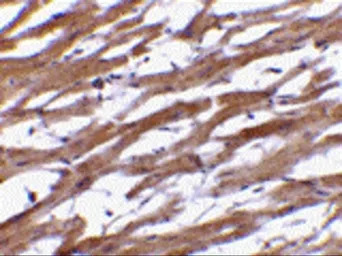

IHC-P analysis of human heart tissue using GTX85073 BAP29 antibody.

Working concentration : 20 μg/ml

Working concentration : 10 μg/ml